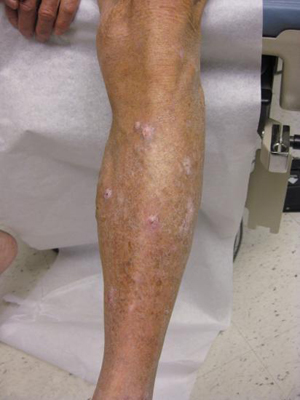

Prurigo nodularis

Clinical features